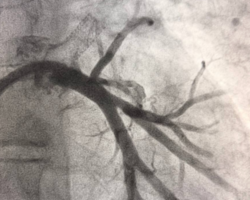

Вмешательство проводилось через бедренный венозный доступ под местной анестезией. Основная сложность операции заключалась в полной окклюзии обеих легочных вен и необходимости точной навигации инструментов в условиях ограниченной визуализации. После реканализации поражённых участков были имплантированы стенты, обеспечившие надёжное восстановление просвета сосудов и полноценный венозный отток из лёгких.

В результате кровоток по левой верхней и левой нижней легочным венам полностью восстановлен. Состояние пациента стабилизировалось, одышка регрессировала. В настоящее время пациент чувствует себя хорошо.